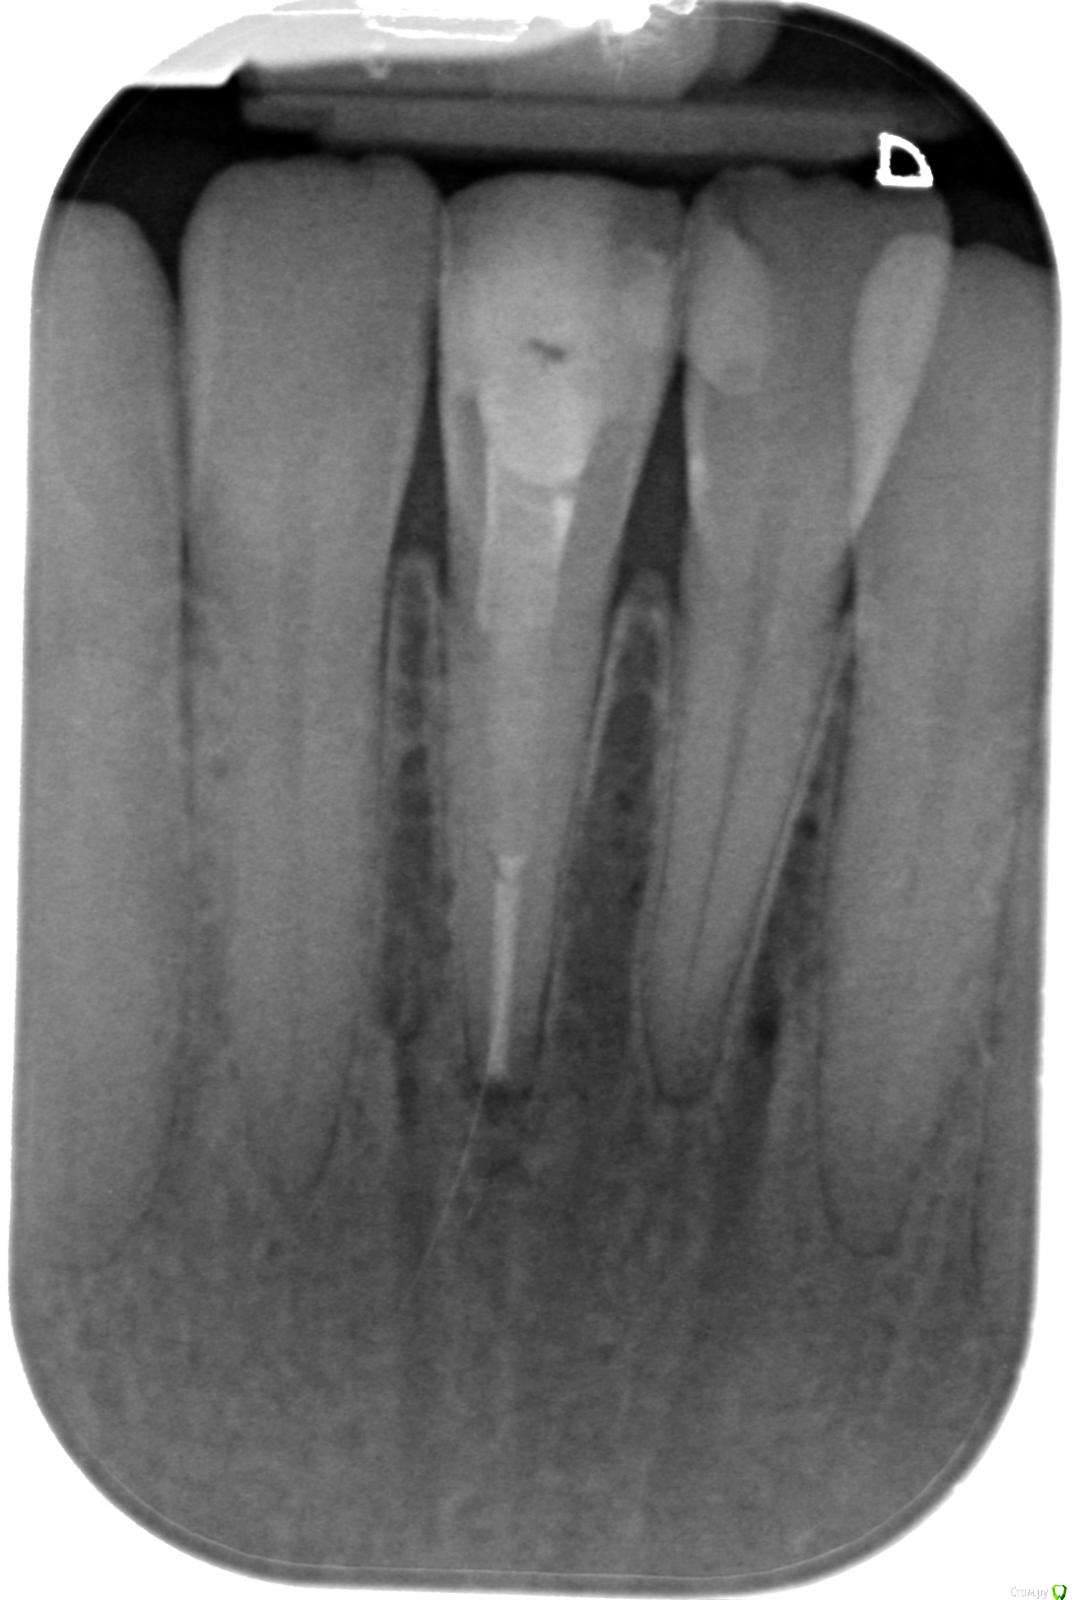

Alexrum Опубликовано 5 февраля, 2021 Поделиться Опубликовано 5 февраля, 2021 (изменено) Здравствуйте, уважаемые доктора!Буду очень благодарна вам за консультацию. Передний нижний зуб справа.Краткая история:1) 15 лет назад зуб лечили как кариес, но поскольку зубы сами маленького размера с тонкой эмалью просвечивал нерв и решили прочистить канал. Пульпита не было. Сразу в течение последующих дней острая пульсирующая боль, на ренгене темное пятно под верхушкой корня. Сказали до конца не прочистили канал, периодонтит.2) в другой клинике стали перелечивать заново. Чистили канал, закладывали лекарство в течение нескольких месяцев, затем постоянное пломбирование гуттаперчей. На снимке гуттаперчевый штифт вышел за верхушку корня на 2 мм, консультирующий хирург сказал делать резекцию в течение года от чего я отказалась.3) Зуб не беспокоил 15 лет. Сейчас на рентгене штифта за верхушкой корня нет, рассосался? В течение нескольких месяцев резкая боль на горячее и периодически пульсирующая. Сегодня была на консультации у опытного эндодонта. Её мнение: верхушка корня запломбирована хорошо, болеть не может. Предложила прочистить верхнюю половину корня зуба, сказала там есть две темные полости, может быть разлом. У врача есть микроскоп. За свою жизнь мне вылечили много периодонтитов в России, очень успешно. Уважаемые доктора, очень важно ваше мнение. Подскажите, пожалуйста, что делать дальше с зубом. Сейчас живу в европе, в Россию приехать пока нет возможности. Огромное спасибо! Изменено 5 февраля, 2021 пользователем Alexrum Ссылка на комментарий

ЛанаМ Опубликовано 7 февраля, 2021 Поделиться Опубликовано 7 февраля, 2021 Ваши жалобы характерны для длительно существующего хронического воспаления пульпы зуба. Обратите внимание на соседний зуб с пломбой, возможно, это он вам дает такую симптоматику. Пломба достаточно близко к нерву, возможен хронический пульпит.Зуб с удаленным нервом может дать такие боли только при наличии дополнительного незалеченного канала, а увидеть этот канал можно только на КТ, рентген дает только одну проекцию. Гуттаперчевый штифт рассосаться не может, скорее всего за верхушку был выведен пломбировочный материал. С ним такое может быть. Ссылка на комментарий

ЛанаМ Опубликовано 14 февраля, 2021 Поделиться Опубликовано 14 февраля, 2021 Здравствуйте, Alexrum. Небольшое воспаление на корне есть. Качество пломбирования хорошее, внутри зуба, по видимому, стекловолоконный штифт. Хотелось бы знать временной интервал между выложенными снимками, чтобы оценить необходимость перелечивания. Обычно зубы с периодонтитом беспокоят при кусании и жевании. Жалобы ваши больше подходят к гангренозному пульпиту, а для него нужно наличие полумертвого нерва в канале, с таким нервом могут сочетаться и гранулемы. В вашем запломбированном зубе давать чувствительность к горячему нечему. Но из любого правила бывают исключения, поэтому без очного осмотра утверждать что-то сложно. Меня больше смущает соседний зуб в этом плане. Ссылка на комментарий